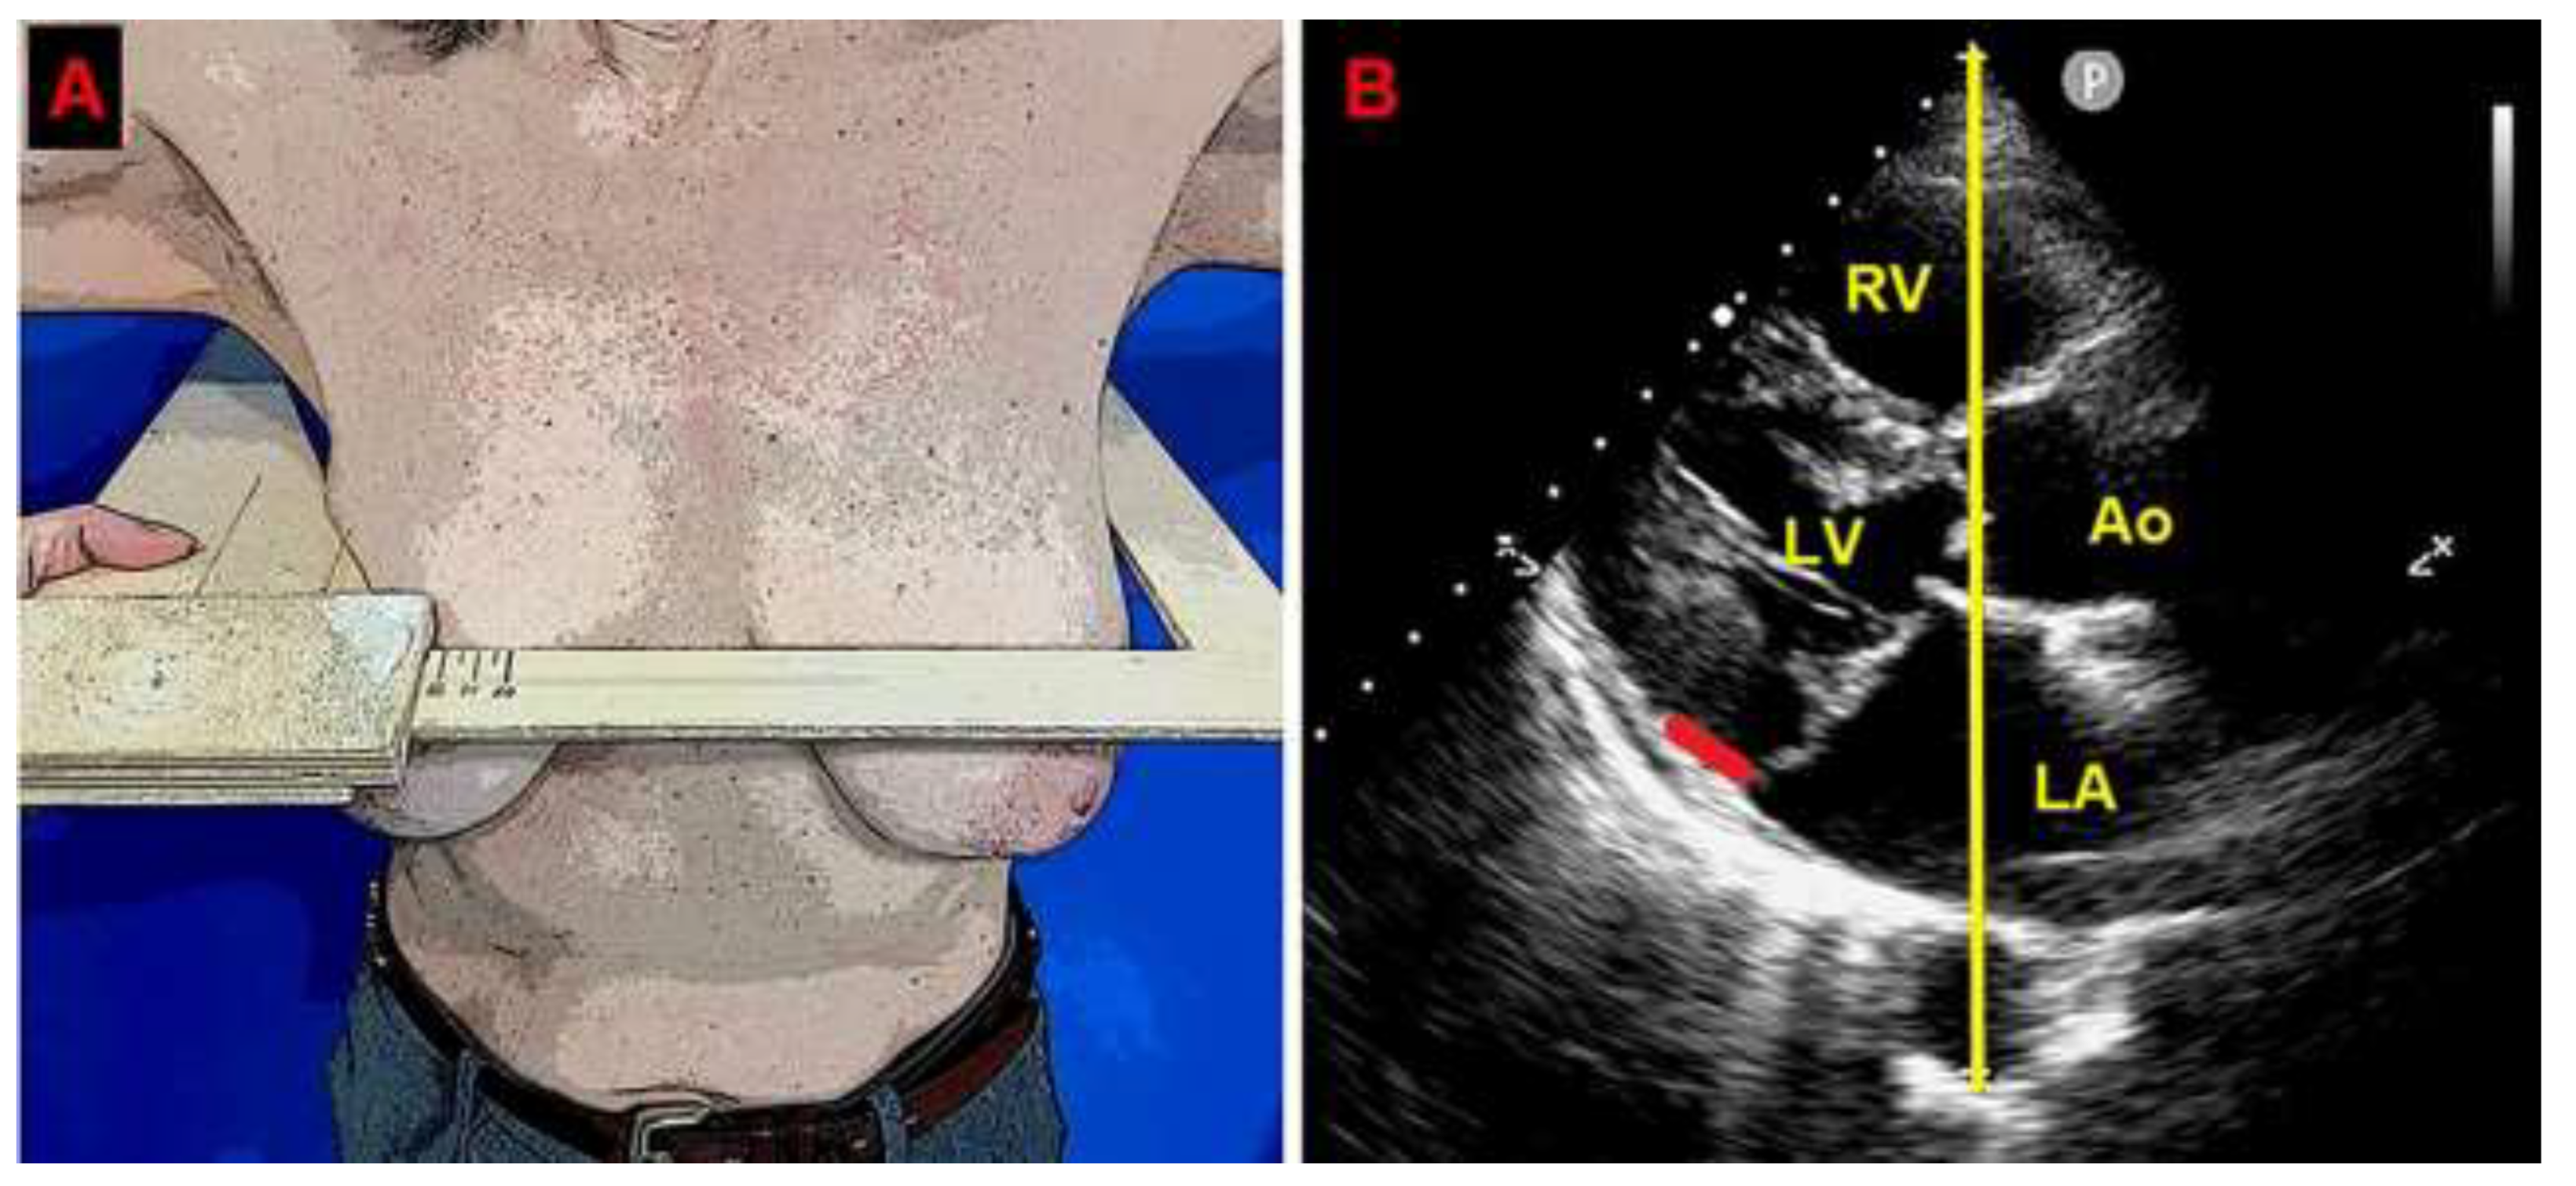

A preliminary chest shape assessment, as noninvasively assessed by the modified Haller index (MHI) [31], obtained by dividing the latero-lateral (L-L) thoracic diameter by the antero-posterior (A-P) thoracic diameter, revealed a concave-shaped chest wall conformation (L-L thoracic diameter = 29 cm, A-P thoracic diameter = 11 cm, estimated MHI = 2.6) (Figure 1).

Figure 1. Modified Haller index, obtained by dividing the latero-lateral thoracic diameter (measured by a rigid ruler coupled to a level) by the antero-posterior thoracic diameter (measured from the echocardiographic parasternal long-axis view, as the distance between the true apex of the sector and the posterior wall of the descending aorta). The bold red line indicates the MAD distance. The bold yellow line indicates the antero-posterior thoracic diameter. Ao, aorta; LA; left atrium; LV, left ventricle; MAD, mitral annular disjunction; RV, right ventricle.